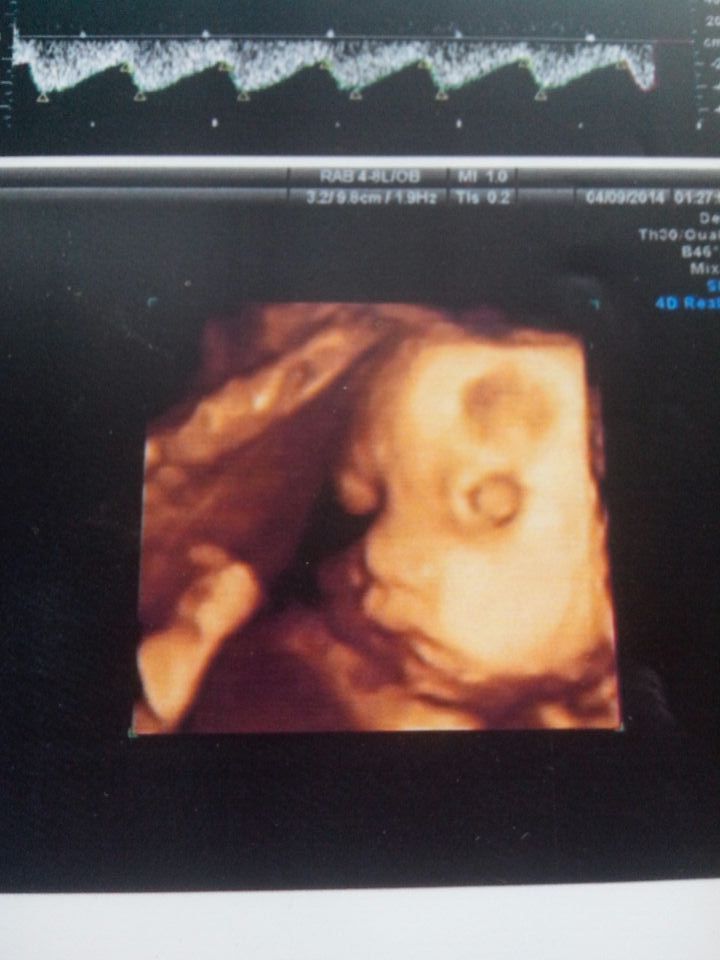

六个半月宝宝刚刚做的四维彩超可额头上有块阴影医生说可能是胎记,家人都担心死了,请大家帮忙看看 点击展开 匿名用户 2014-04-09 08:28 为您推荐: 其他回答 病情分析: 你好,根据你的描述,这个目前很难确诊。 指导意见: 即使是胎记也没有关系的,等宝宝生下来后可以通过激光去除。 匿名用户 2014-04-09 08:30 相关问题 怀孕33周的时候宝宝做了四维彩超 眼睛那里一块黑色阴影 会不会是胎记啊 宝宝额头上,好大一块紫色,是不是胎记